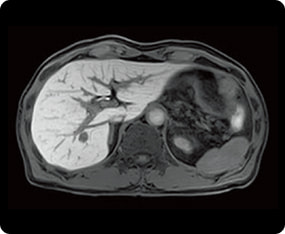

その他MRI検査の症例画像

腹部

必要に応じて放射線専門医による画像読影も行っています。脳や脊髄などの神経の検査に加え、関節(四肢)、腹部(肝臓・胆嚢・膵臓)、前立腺など、全身のさまざまな部位の精密検査に対応可能です。